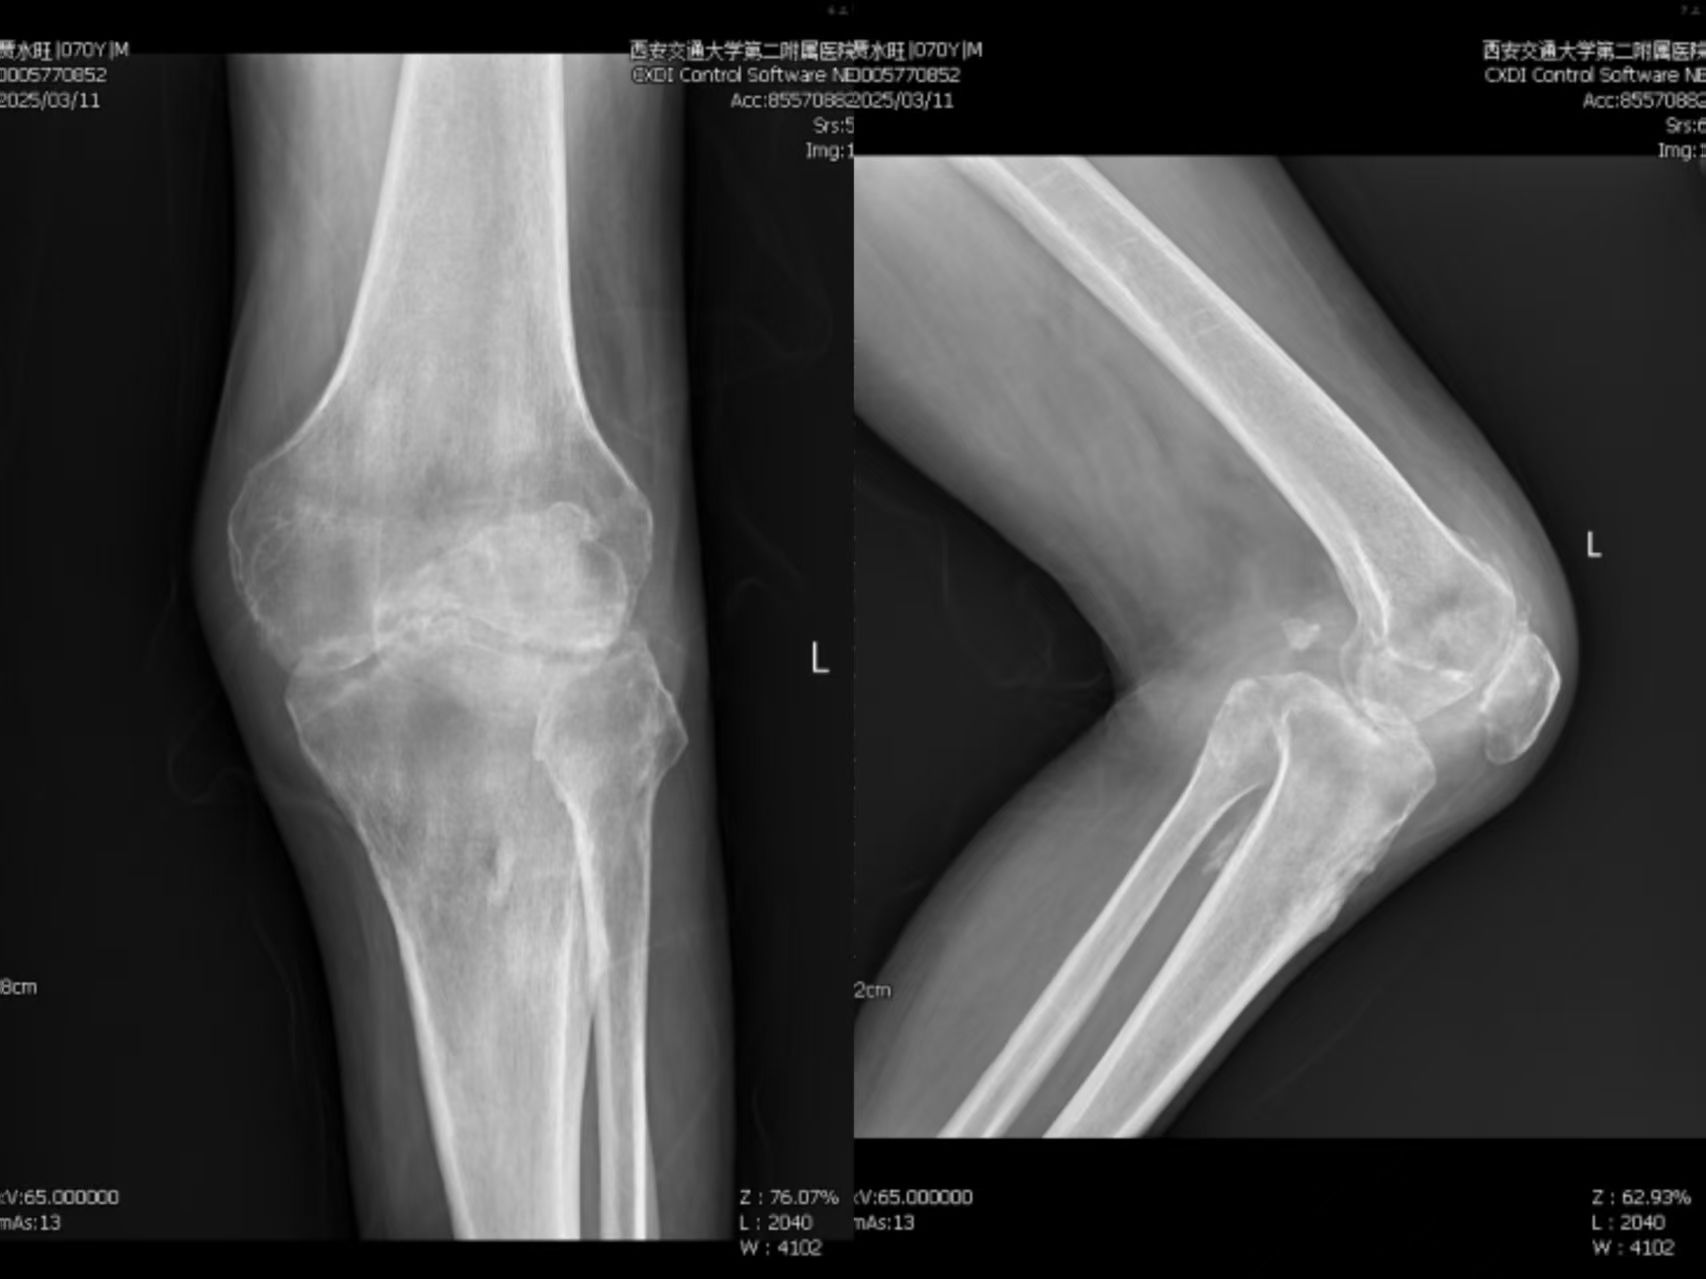

术前患者左膝关节X线正侧位片